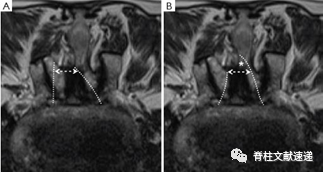

图注:术前(A)和最后随访(B)MRI对小关节保存的测量。虚线突出显示椎板切开的范围。小关节保存率=y/x×100%。

图注:对一例严重退行性腰椎管狭窄症患者行UBE减压术后的最终随访MRI(B)与术前MRI(A)对比显示,减压充分,硬膜横截面积和双侧小关节的保存改善明显。